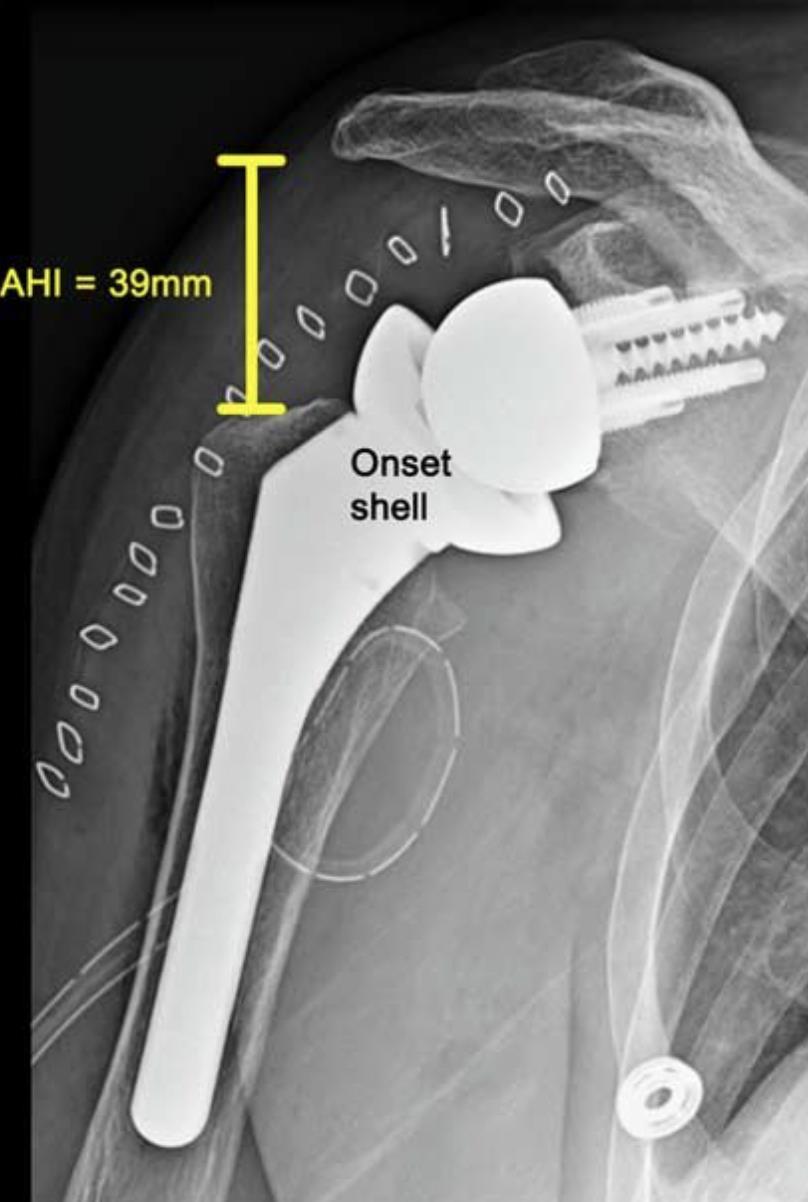

[Blocked from Release] AltiVate Reverse®

• The AltiVate Reverse Shoulder System by Enovis is a reverse shoulder arthroplasty platform designed to restore mobility in patients with rotator cuff deficiency by optimizing implant fit and fixation.

• It uses a lateralized center of rotation and a 135° humeral neck-shaft angle to improve range of motion and reduce complications like scapular notching.

• The system incorporates modular components and precision instrumentation to better match patient anatomy and support stable long-term fixation.